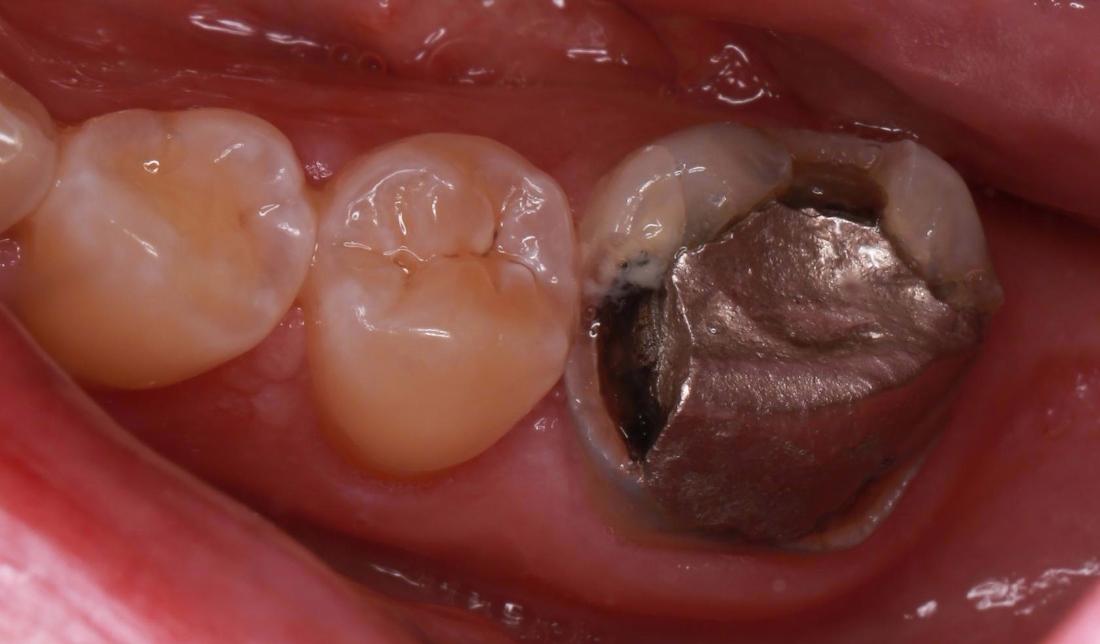

This patient came in with a large filling on the back molar that was becoming decayed. To save the remaining structure of the tooth Dr Kiaee used a dental crown to cover the existing tooth and restore the integrity.

A crown can be used to cover a weak or damaged tooth. Besides strengthening a damaged tooth, a crown can improve the tooth's appearance, shape and colour.